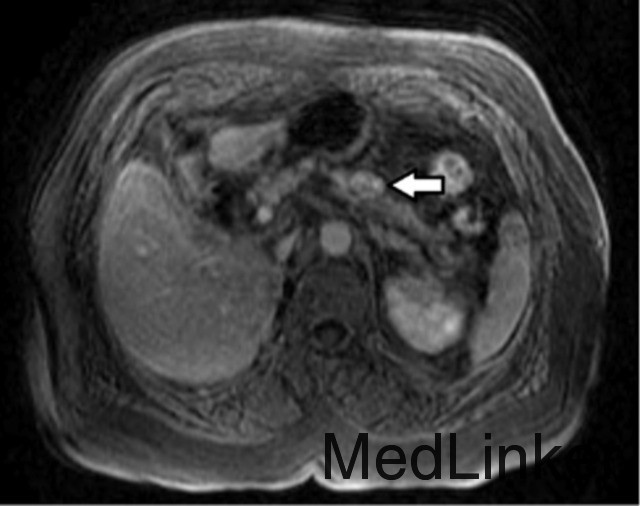

CT 显示在胰腺体上出现 20 mm 占位 (图 a)。MRI 显示在胰体胰尾之间出现 20×13 mm 实性结节,增强 MRI 提示神经内分泌源性 (图 b)。生长抑素闪烁照相显示在胰腺和右侧甲状腺生长抑素受体异常高表达。通过脑部 MRI 检查结果显示为正常,可排除 Von Hippel-Lindau 综合征 (VHLD)。